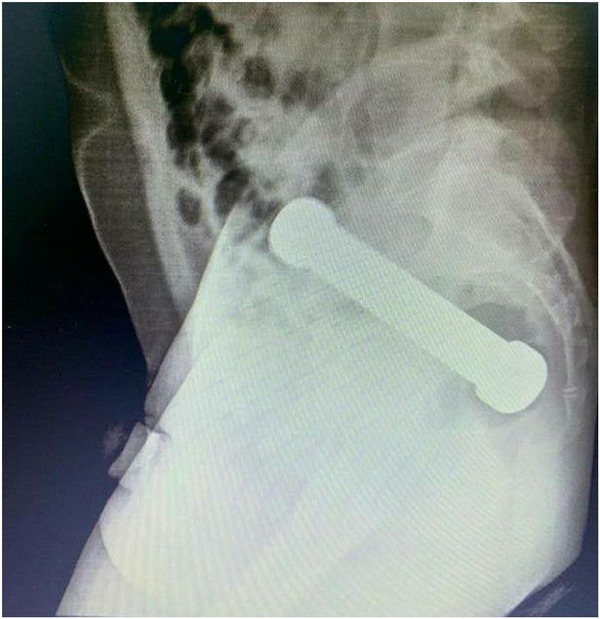

しかしこの男性は医師らの質問に対してなぜか非協力的で、痛みの原因も判明しなかったことから、男性の下腹部のレントゲン写真を撮ったところ、体内にダンベルが入っているのを発見して驚愕したそうです。

男性は尻の中にダンベルが挿入されていることを医師に一切報告しなかったそうです。

結局医師らは手術で取り除くのは不可能と判断し、指で便を掻き出す方法でダンベルを取り出したとのこと。